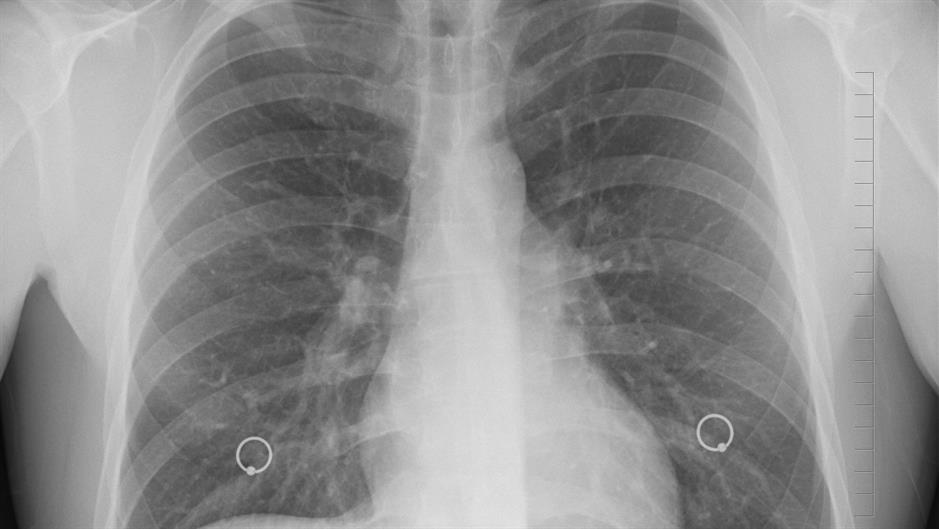

U do 25% ljudi koji su dobili rak pluća, rak se otkrije slučajno na rutinskoj RTG snimci pluća ili CT, ali postoje i simptomi na koje biste trebali obratiti pažnju: